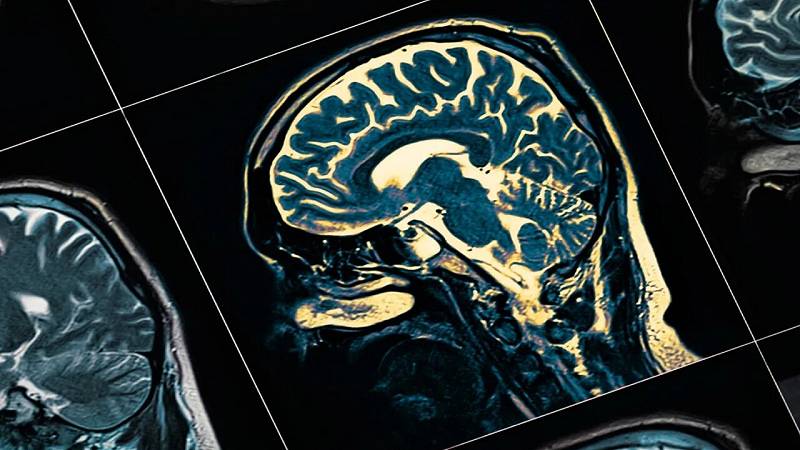

Alzheimer, uno studio mostra criticità nelle comunità rurali americane